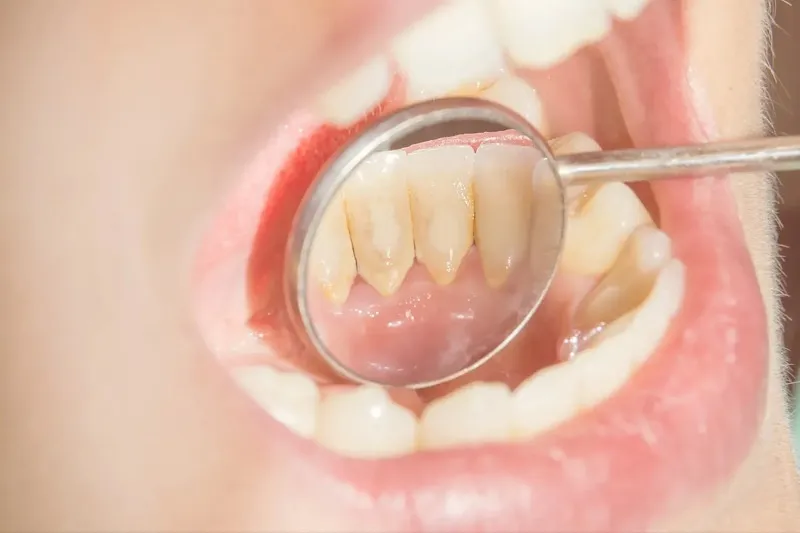

Cao răng là những mảng bám bám chặt vững chắc vào bề mặt răng theo thời gian. Tuy nhiên, nhiều người vẫn còn chủ quan việc chăm

Cao răng bị vỡ là hiện tượng khá phổ biến, nhưng không phải ai cũng biết cách xử lý đúng cách khi gặp phải tình trạng này.